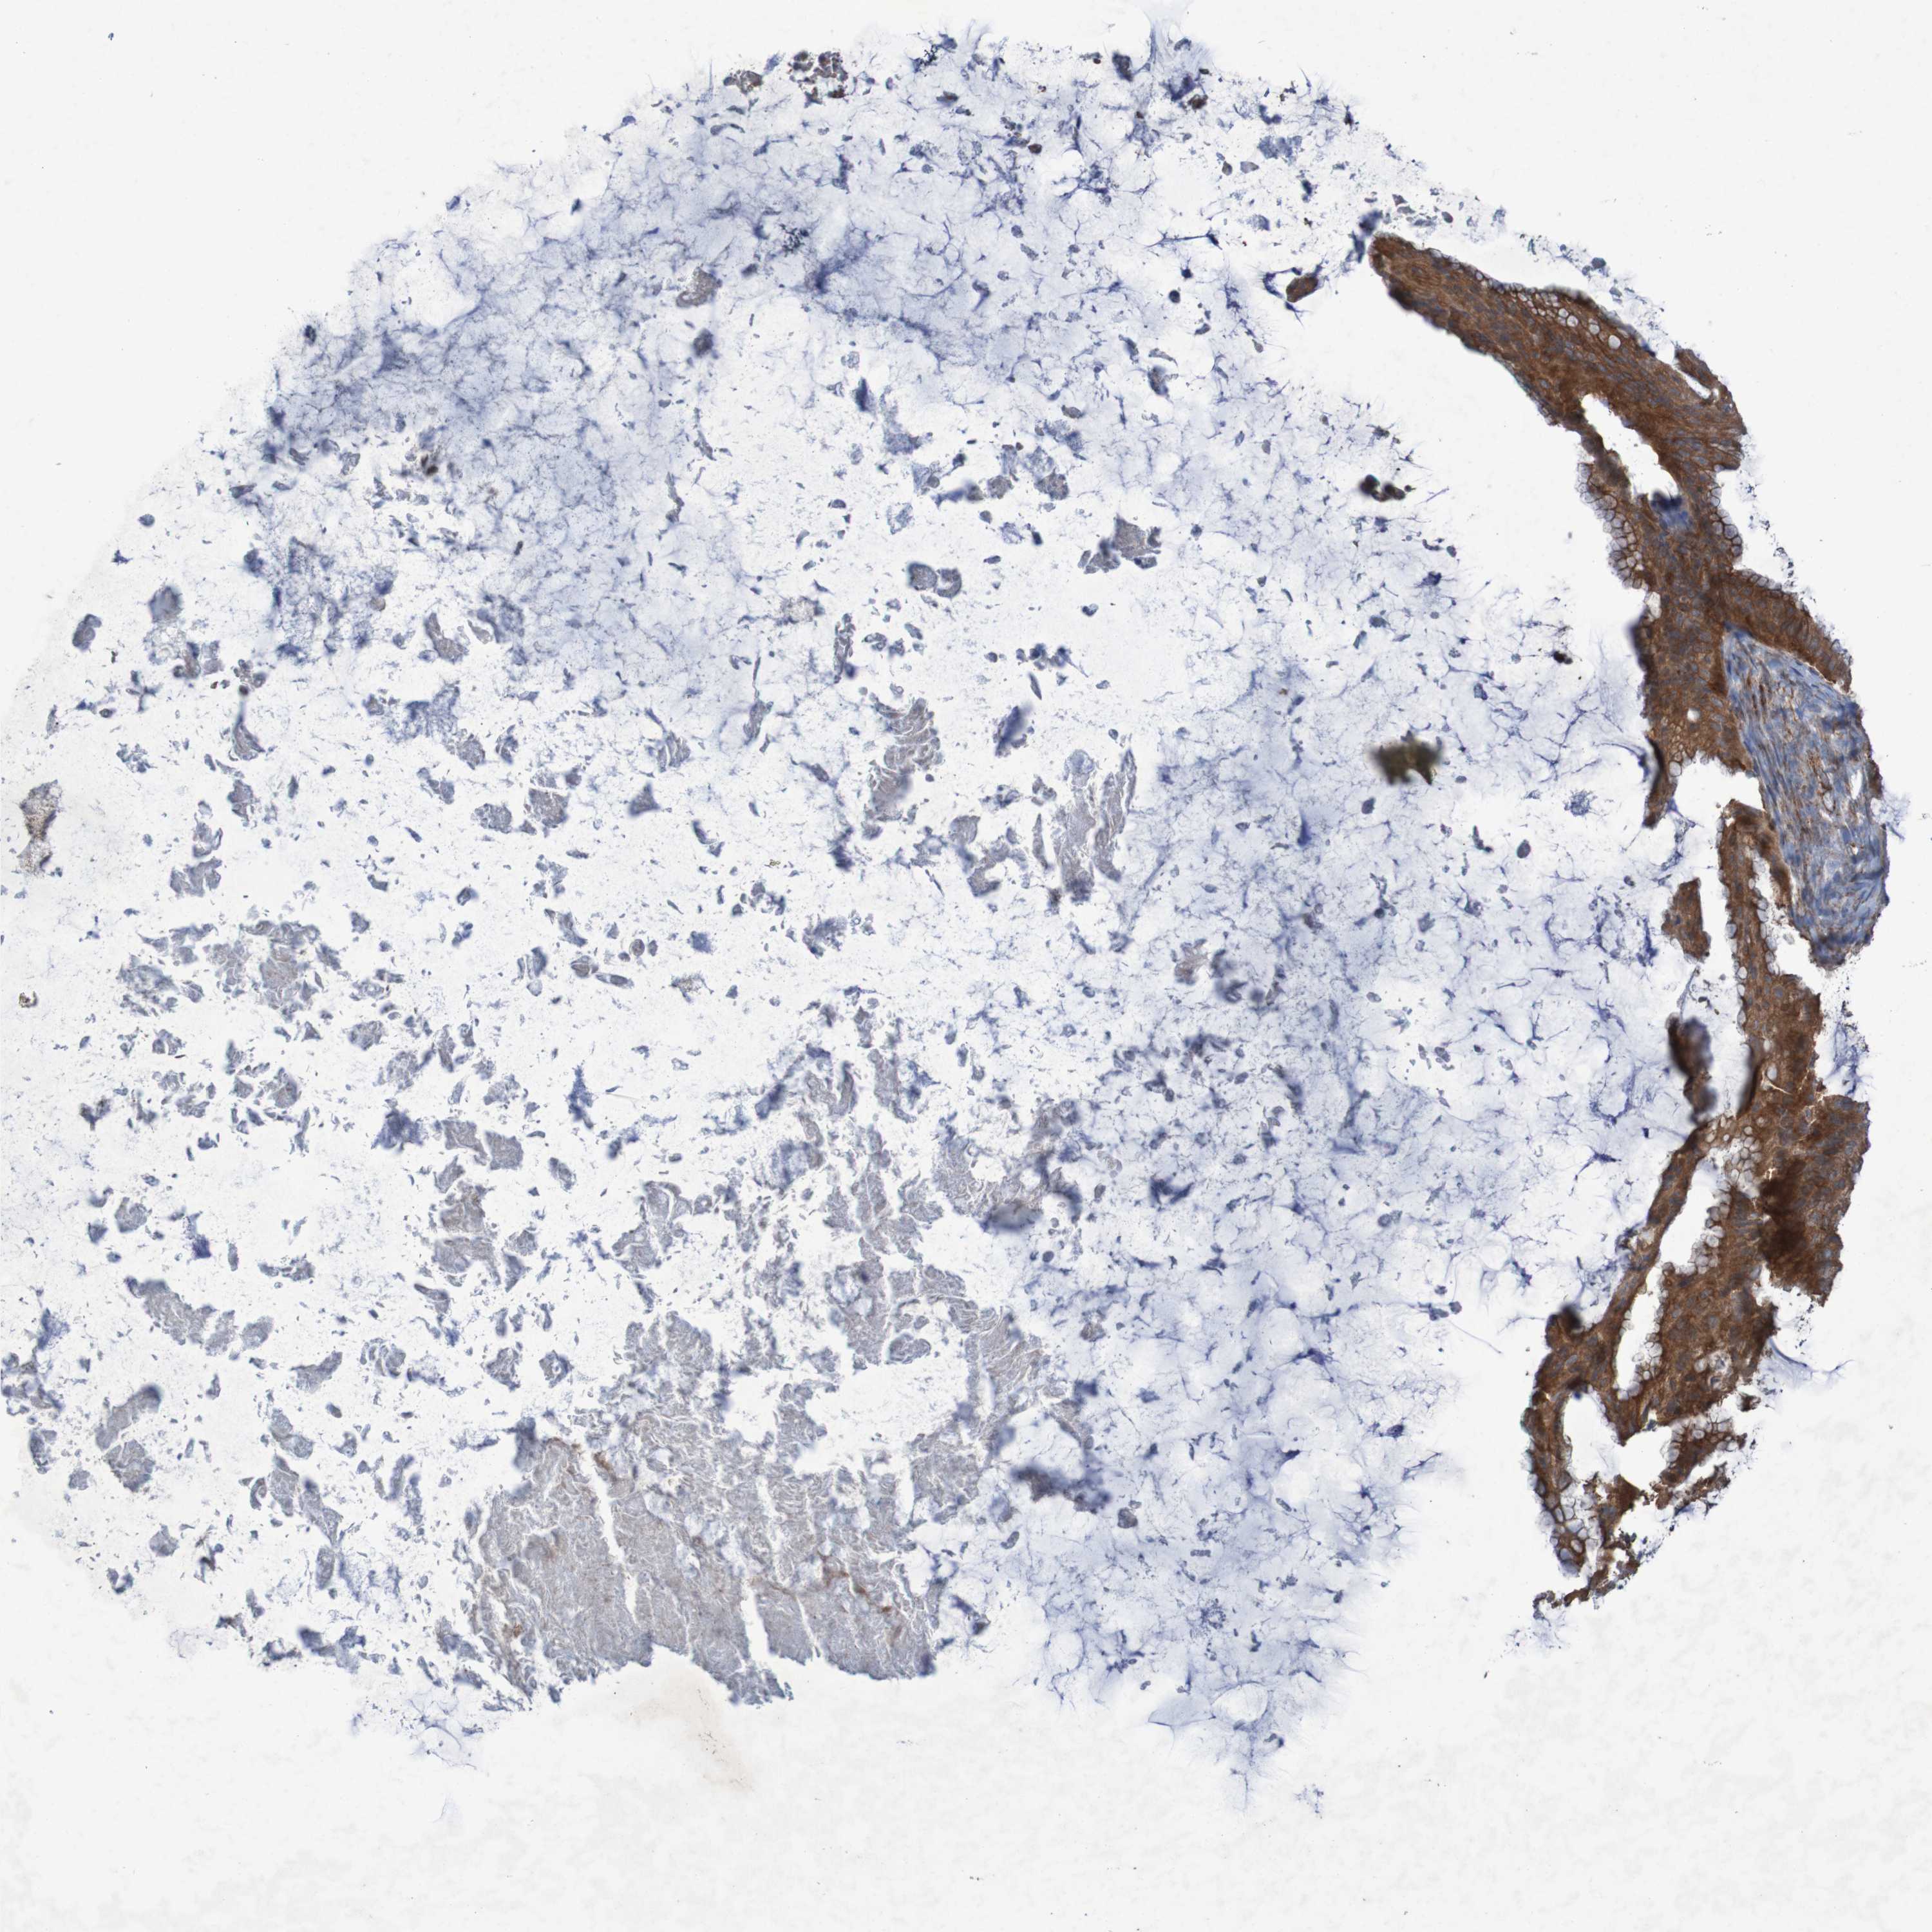

OVARIAN CANCER - Protein expressioni

A mouse-over function shows sample information and annotation data. Click on an image to view it in a full screen mode. Samples can be filtered based on level of antibody staining by selecting one or several of the following categories: high, medium, low and not detected. The assay and annotation is described here.

Note that samples used for immunohistochemistry by the Human Protein Atlas do not correspond to samples in the TCGA dataset.

Antibody stainingi

Antibody staining in the annotated cell types in the current human tissue is reported as not detected, low, medium, or high, based on conventional immunohistochemistry profiling in selected tissues. This score is based on the combination of the staining intensity and fraction of stained cells.

Each image is clickable and will lead to virtual microscopy that enables deeper exploration of all samples and also displays staining intensity scores, fraction scores and subcellular localization as well as patient and tissue information for each sample.

Antibody HPA010980

Antibody HPA011408

Staining

High

Medium

Low

Not detected

Intensity

Strong

Moderate

Weak

Negative

Quantity

>75%

75%-25%

<25%

None

Location

Nuclear

Cytoplasmic/membranous

Cytoplasmic/membranous,nuclear

Cystadenocarcinoma, serous, NOS

Carcinoma, endometroid

Cystadenocarcinoma, mucinous, NOS

Carcinoma, NOS